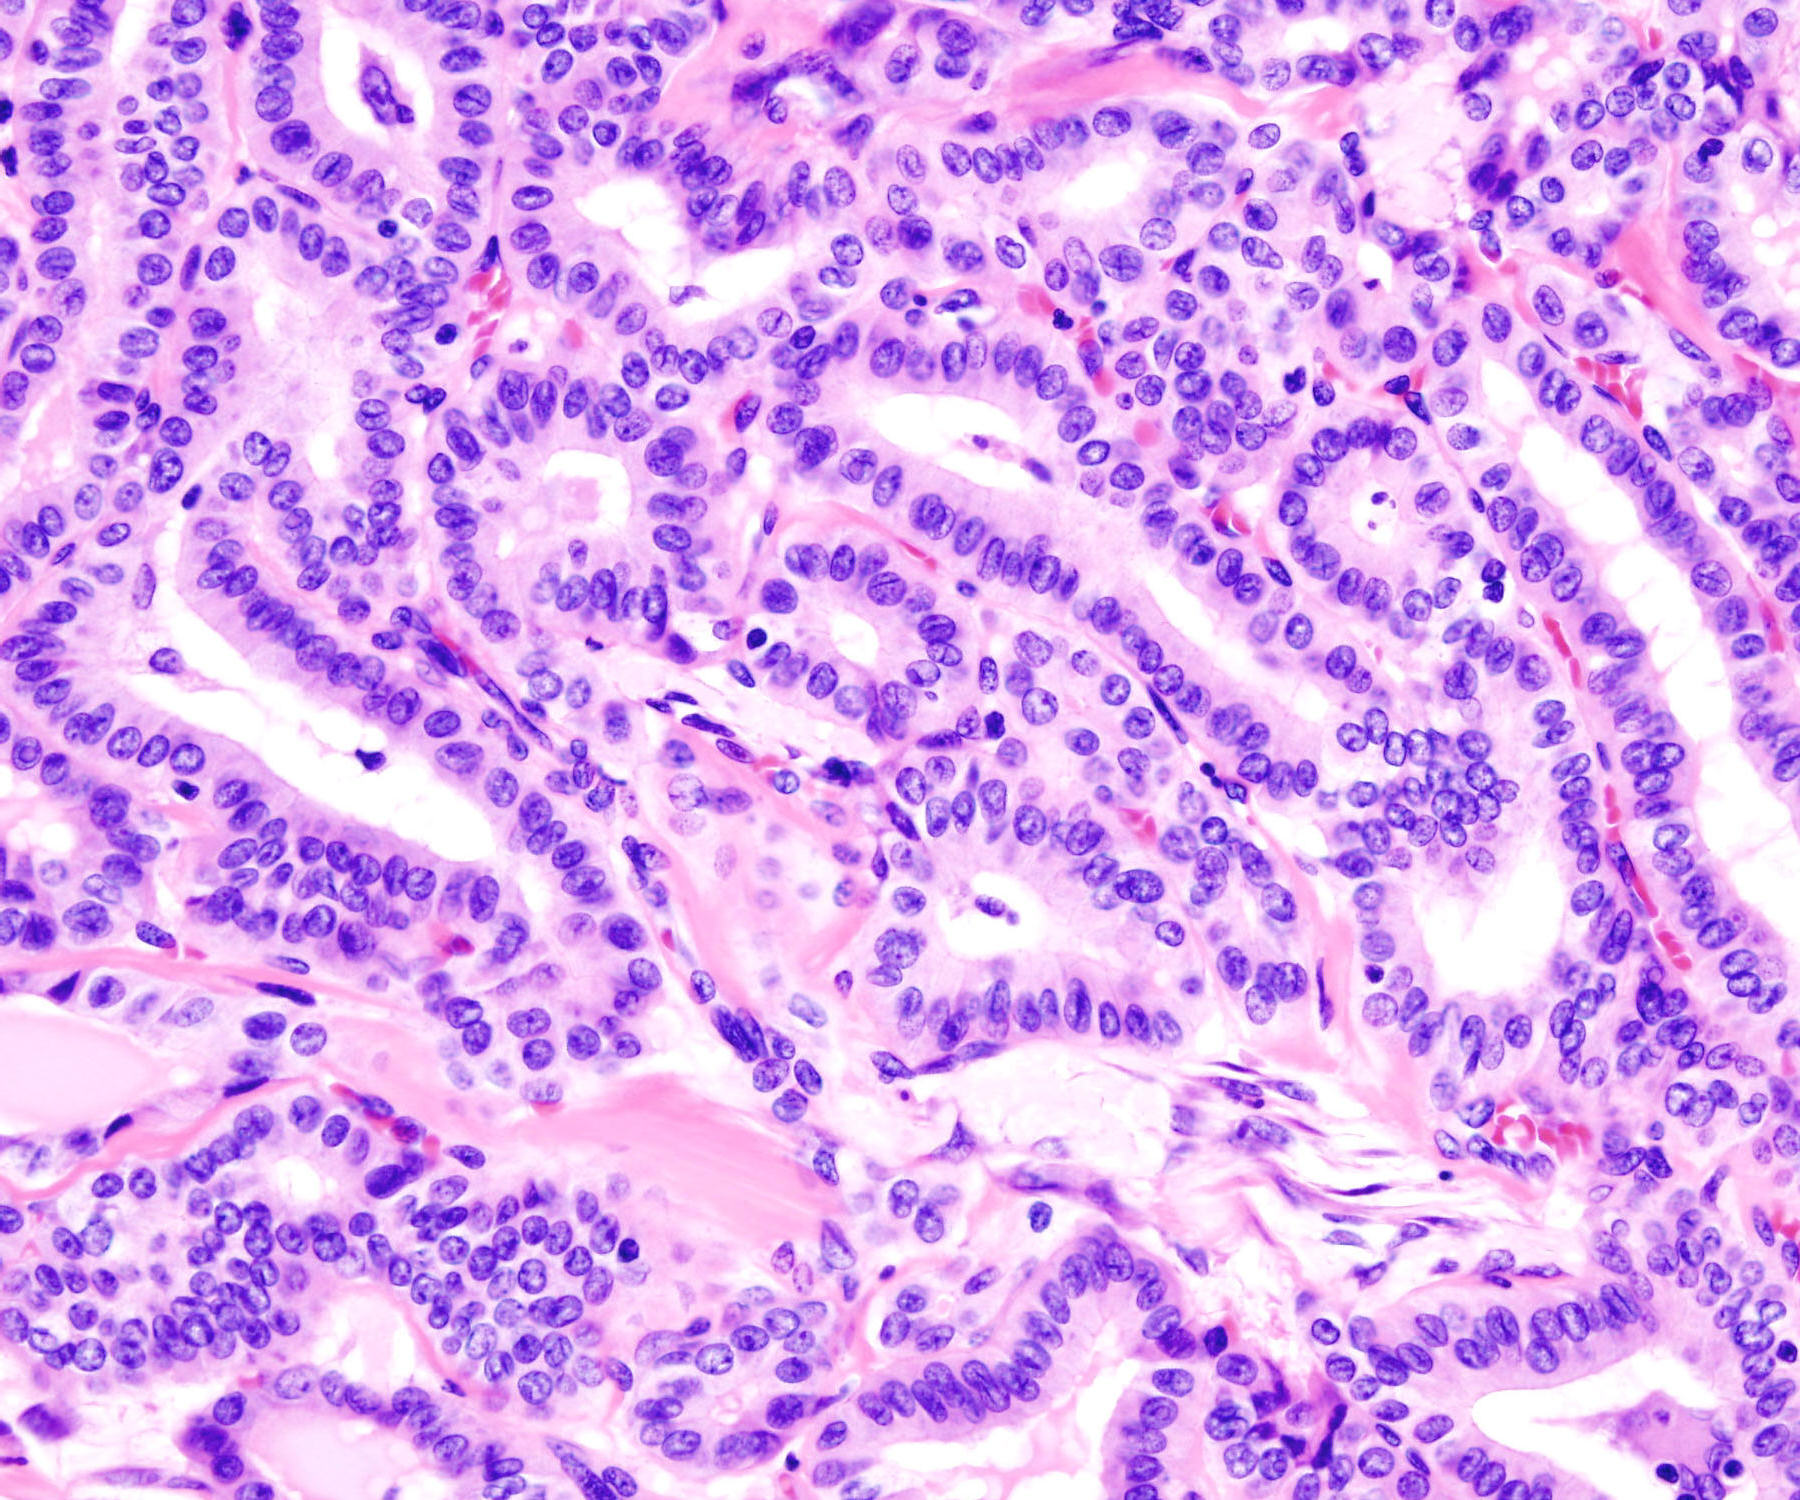

Papillêre karsinoom van die tiroïed

Thyroid papillary carcinoma

Thyroid_papillary_carcinoma_histopatholgy_(2)